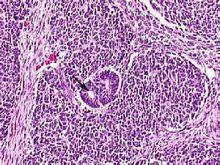

松果體母細胞瘤是一種高度惡化,發生於兒童的原始胚胎性松果體實質性腫瘤,瘤細胞小,核圓或是不規則,緻密,不定形片狀排列。松果體細胞瘤是發生於松果體實質細胞的腫瘤,可見於任何年齡組,但大多發生於25~35歲年齡段,兒童多為松果體母細胞瘤。男女性別比例基本相等。

松果體母細胞瘤是顱內罕見的腫瘤,約占松果體腫瘤的45%。本病可出現於任何年齡,但是常常是以20歲以前多見,好發於兒童,以男性稍多見。